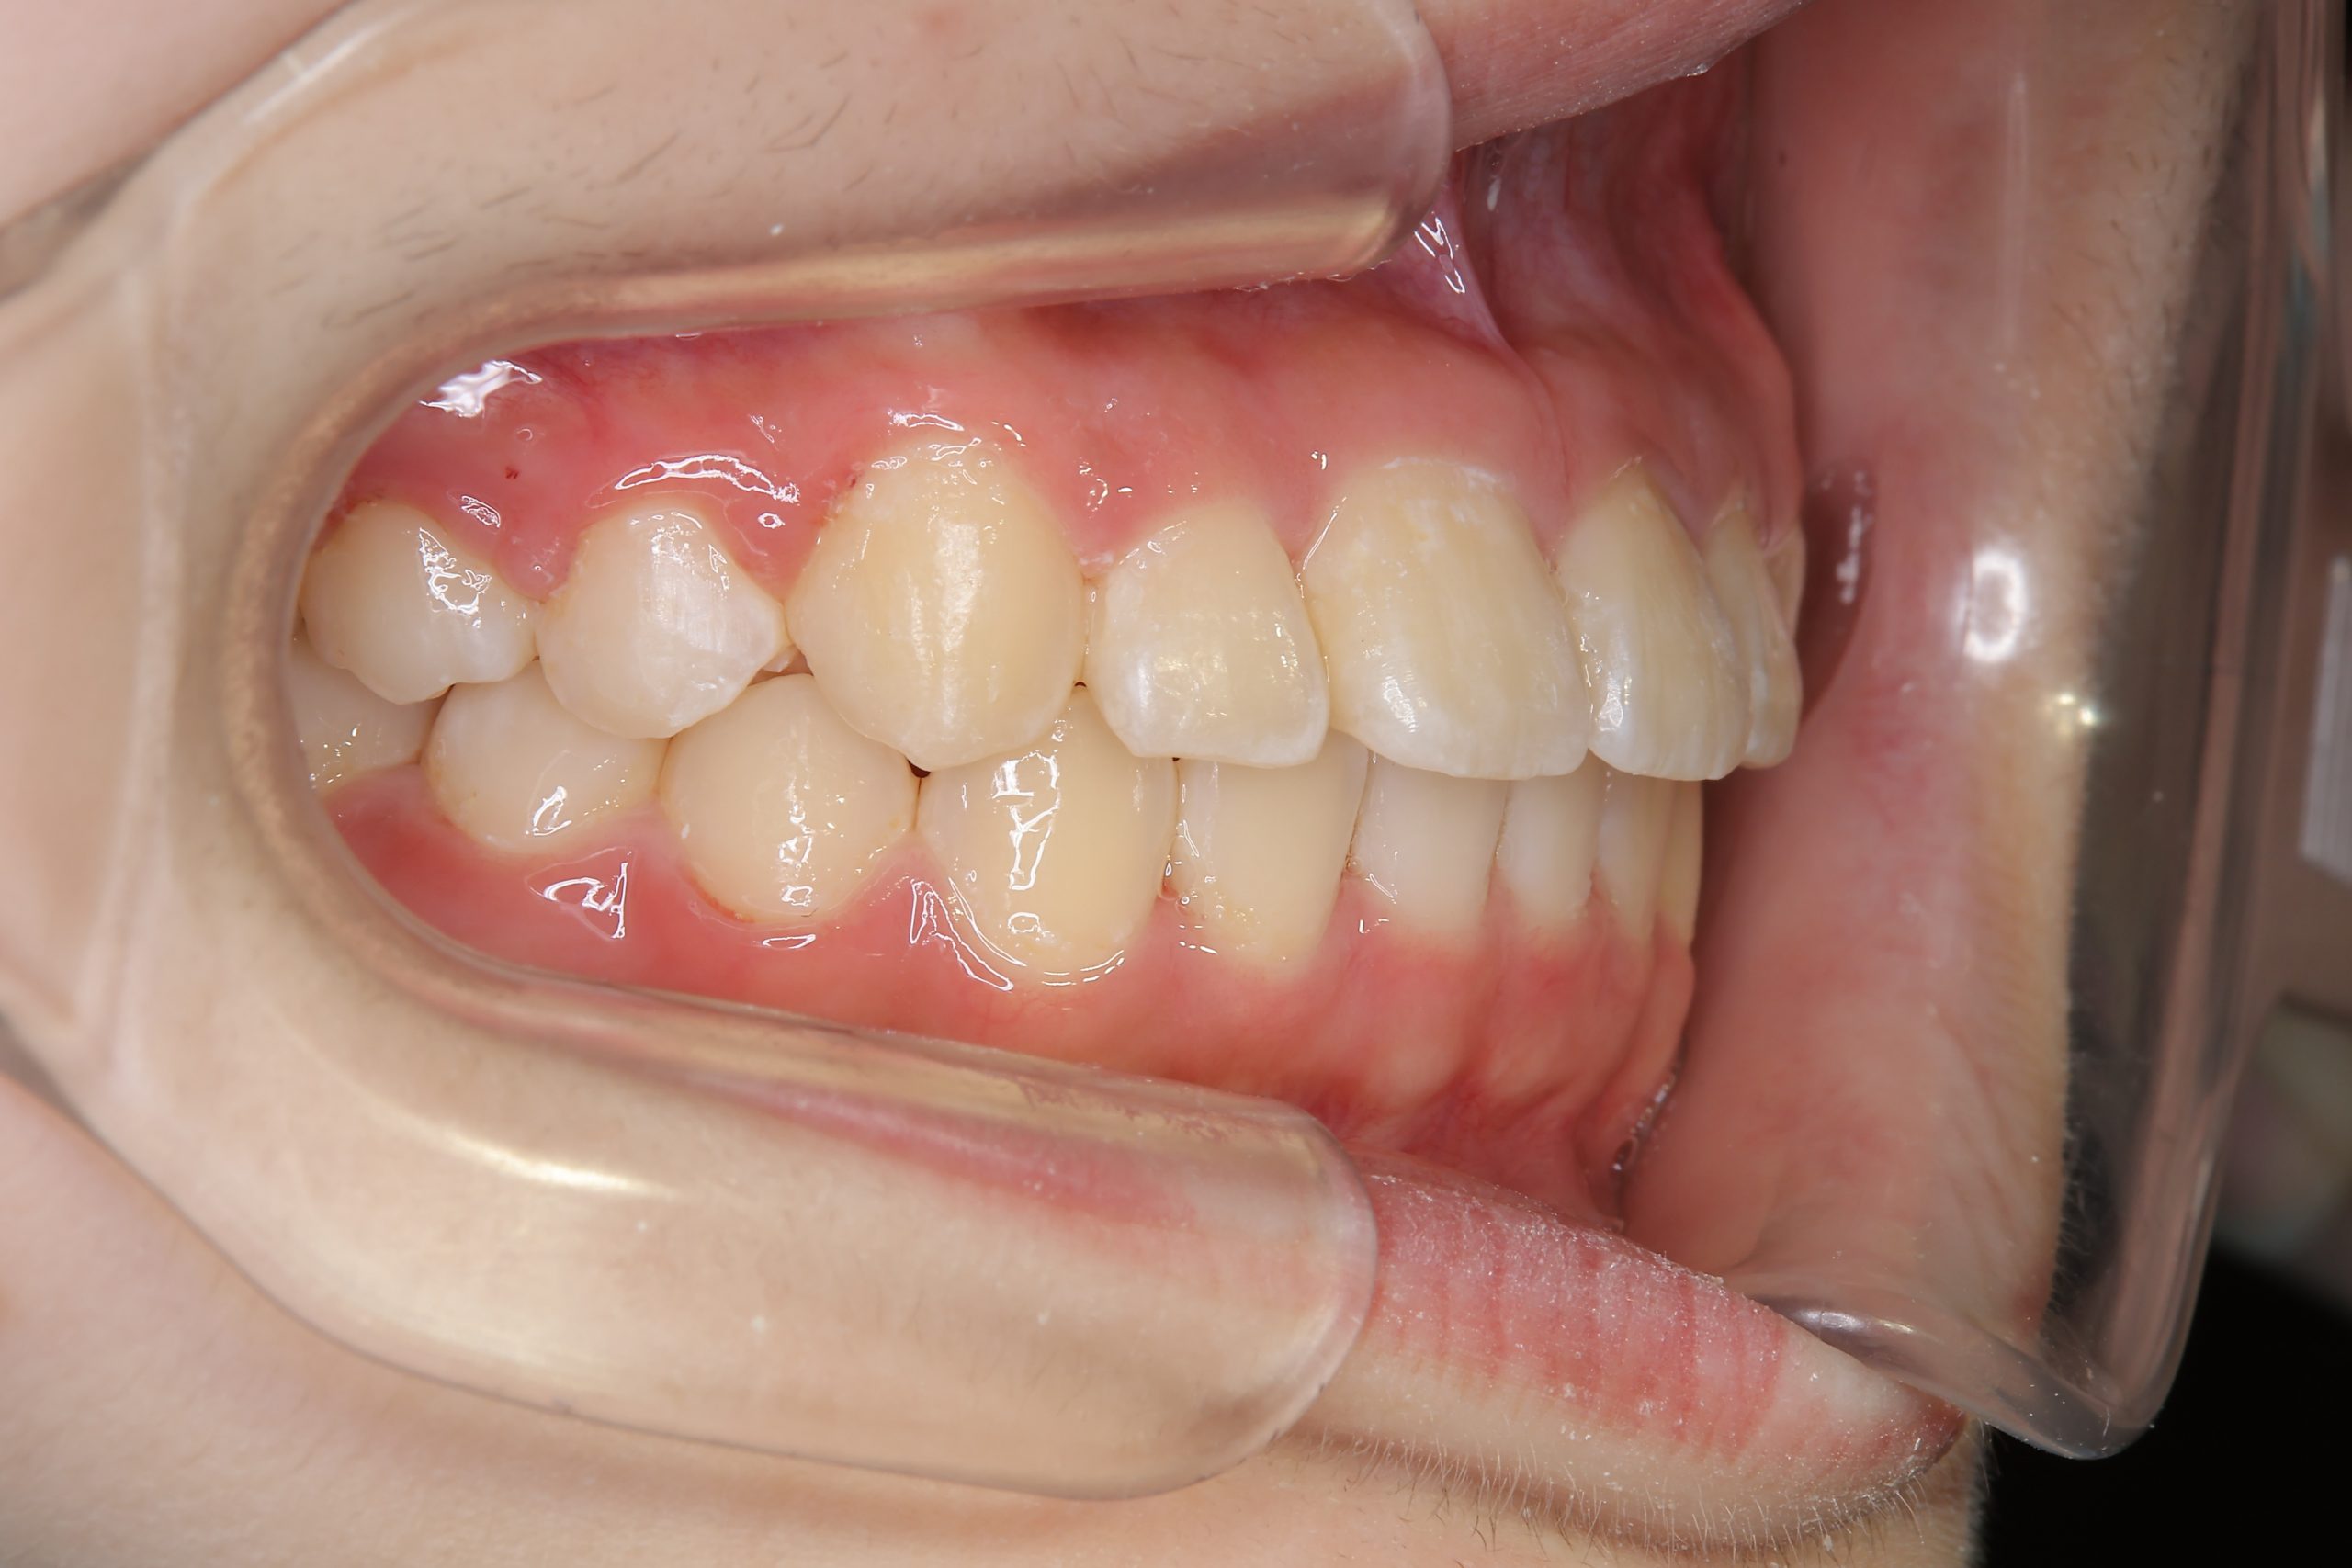

アフター

全顎ワイヤー矯正 症例_805

主訴 中心から前歯がずれている

施術内容 成人矯正1期治療

治癒期間 1年3か月間

費用 954,800円(税込)